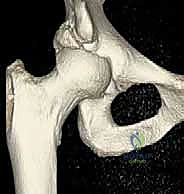

لفهم أهمية جراحة منظار الورك، يجب أولاً أن نفهم التكوين التشريحي المعقد لهذا المفصل الحيوي. مفصل الورك هو مفصل من نوع "الكرة والتجويف" (Ball and Socket Joint).

* الكرة: هي رأس عظمة الفخذ (Femoral Head).

* التجويف: هو جزء من عظمة الحوض يُعرف باسم الحُق (Acetabulum).

يُغطى كل من الكرة والتجويف بطبقة ناعمة من الغضروف المفصلي الذي يسمح للعظام بالانزلاق بسلاسة فوق بعضها البعض. كما يحيط بحافة التجويف حلقة من الغضروف الليفي القوي تُسمى الشفا الغضروفي (Labrum). يعمل الشفا كختم مطاطي يحافظ على السائل الزلالي داخل المفصل ويزيد من استقراره.

1. الاصطدام الفخذي الحقي (Femoroacetabular Impingement - FAI)

وهي حالة شائعة جداً تحدث عندما تنمو نتوءات عظمية زائدة إما على رأس عظمة الفخذ (Cam) أو على حافة تجويف الحوض (Pincer)، أو كليهما. هذا النمو الزائد يؤدي إلى احتكاك غير طبيعي أثناء الحركة، مما يمزق الشفا الغضروفي ويتلف الغضروف المفصلي.